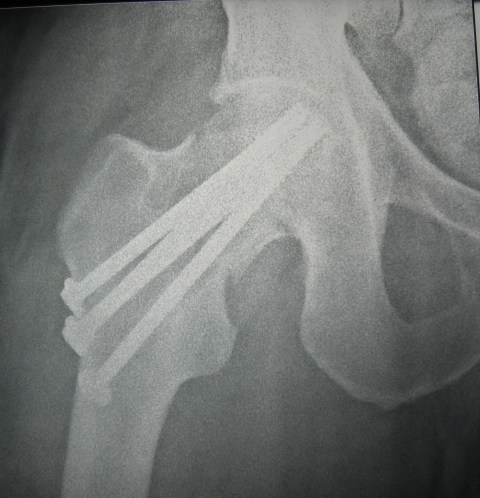

my-fracture-2-postop-a